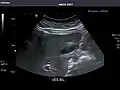

Kidneys: Right and left kidneys measure 11.5 cm and 12 cm in length respectively. No hydronephrosis. Small left lower pole kidney cyst.

Right kidney -